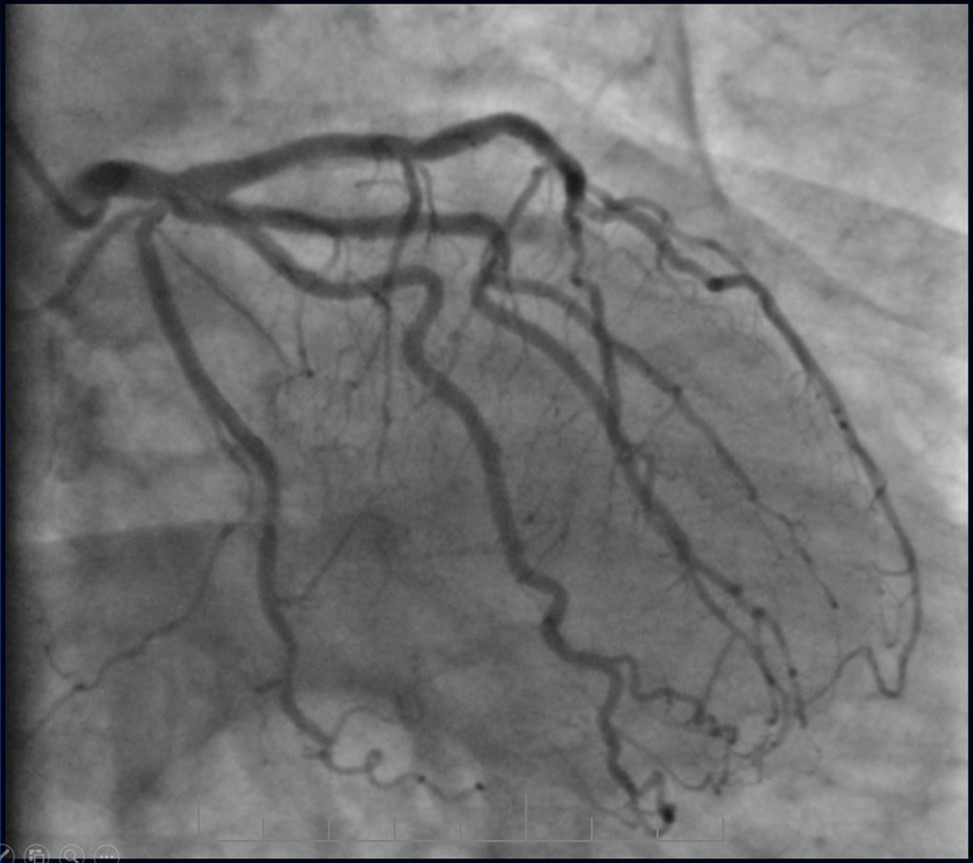

Angiography revealed rare anatomical variation LMCA quadrifurcation (Figure 1, Figure 2), 50% stenosis of the distal part of the LMCA, 40% stenosis of the ostial segment of left anterior descending (LAD) artery and diffuse prolonged 70-75-95% stenosis in mid-segment (Figure 3), 75% stenosis of the ostial segment of the circumflex (CX) artery, 75% stenosis of the ostial segment of the first marginal branch (OM1), 75-90% stenosis of the proximal segment of the intermediate artery (IMA), prolonged diffuse severe 90-95% stenosis of mid-segment of the right coronary artery (RCA) (Figure 4).

Figure 1.Quadrifurcation of the left main coronary artery

Quadrifurcation of the left main coronary artery

Subsequent coronary angiography eight months after the last PCI revealed patent stents with mild, non-significant restenosis in DES and 50-60% in-stent restenosis in BMS (Figure 13, Figure 14).

Figure 14.Left coronary artery, follow-up CAG eight months after last PCI.

Left coronary artery, follow-up CAG eight months after last PCI.